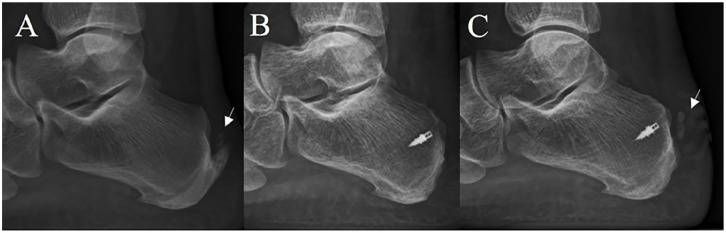

Methods: A retrospective cohort study was performed in order to determine clinical and radiographic outcomes of PMGR and ATDR for patients presenting with symptomatic calcified IAT, at a minimum follow-up of 30 months. Patient satisfaction was assessed at last available follow-up as very satisfied, satisfied, and unsatisfied. Clinical assessment was performed evaluating preoperative and last available follow-up visual analog scale for pain (VAS-P) and the Foot and Ankle Outcome Score (FAOS). Radiographic evaluation included Fowler-Phillip angle, calcification length, calcification width, and presence of Achilles IC, measured on standard weightbearing lateral calibrated radiograph of the foot preoperatively and last available follow-up evaluation for each patient.

Results: The mean follow-up was 46 (range, 30-72) months. We registered 45 "very satisfied" patients (84.91%), 6 "satisfied" patients (11.32%), and 2 "unsatisfied" patients (3.77%), as well as statistically significant improvement on both clinical scores tested. We found statistically significant differences between the initial evaluation and last available follow-up on all radiographic measurements. There was no significant radiographic recurrence of calcified IAT, whereas minor Achilles intratendinous calcifications were found in 10 patients (18.87%).